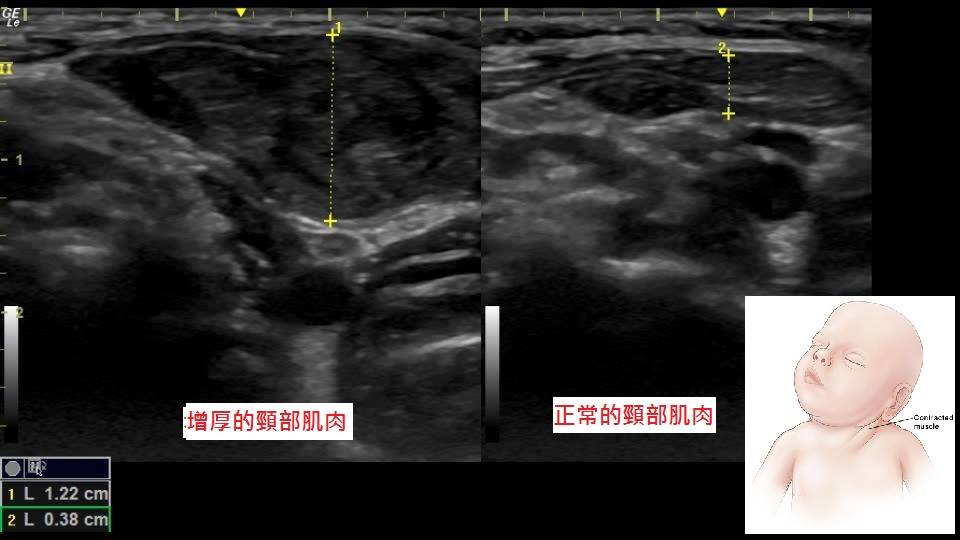

嬰兒斜頸,超音波下可以發現頸部肌肉肥厚,是正常側肌肉的3倍大。

【圖6】嬰兒斜頸,超音波下可以發現頸部肌肉肥厚。